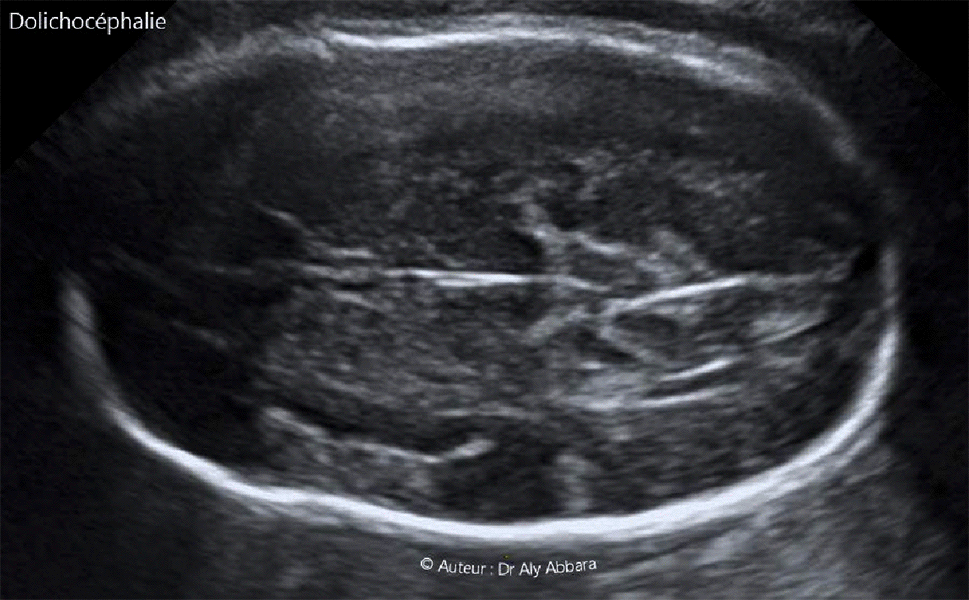

Dolichocéphalie - 32 SA - Echographie

Images échographiques montrant un crâne fœtal dolichocéphale (à 32 SA ; en présentation du siège).

Index céphalique = 61

Description : Il s'agit d'un crâne allongé d'avant en arrière, de forme ovulaire ; la plus grande longueur (diamètre occipito-frontale) l'emporte d'environ d'un quart sur le plus grande largeur (diamètre bi-pariétal).

Chez le fœtus, la dolichocéphalie acquise est fréquemment rencontrée en cas de présentation fœtale non céphalique (siège ou transverse) ; elle se corrige rapidement dans la période post-natale.

En biométrie échographique obstétricale la dolichocéphalie est définie par un index céphalique inférieur à 75,9 et la brachycéphalie (crâne court d'avant en arrière) est définie par un index céphalique supérieur à  80.

L'index (ou indice) céphalique (IC) de Hadlock = (BIP/DOF) x 100

BIP = diamètre bipariétal ; DOF = diamètre occipito-frontal.